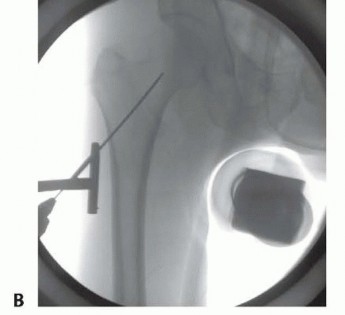

A small incision, usually 3 to 4 cm long, is made several centimeters proximal to the tip of the greater trochanter to allow passage of the nail ( TECH FIG 4). A periosteal elevator can be used to spread the gluteus medius fibers in line with the incision. Blunt dissection with an elevator or a finger provides access to the starting point. The tip of the greater trochanter is palpated. The tendon of the gluteus medius attaching to the trochanter can be felt and is protected.

Using fluoroscopy, a starting point is obtained for the nail at the medial edge of the greater trochanter for a trochanteric-starting cephalomedullary nail. The starting point should be just lateral to the piriformis fossa ( TECH FIG 5A). Alternatively, an awl can also be used to obtain the proper starting point; this can be especially useful in obese patients. An anatomic reduction of the femoral neck must be achieved before reaming. If an anatomic reduction cannot be achieved by closed means, an open reduction must be performed.

---

TECH FIG 4 • Landmarks for cephalomedullary nail placement. The iliac crest is marked and the trochanter is outlined. The incision is in line with the femoral shaft and several centimeters proximal to the tip of the trochanter. This can be done by a Smith-Petersen or Watson-Jones approach, as described earlier. An antirotational pin may be used to maintain reduction ( TECH FIG 5B,C). Once reduction has been obtained, the entry reamer is introduced ( TECH FIG 5D). For a short cephalomedullary nail, the entry reamer is all that is needed before nail passage. If a long cephalomedullary nail is being placed, serial reaming can be performed to 1 to 1.5 cm over the desired nail diameter. ### Proximal and Distal Interlocking After the nail is positioned at the correct depth, the guidewire into the femoral head is placed. Multiple fluoroscopic images are needed to make sure the tip of the guidewire is placed within the center of the femoral head for nails with a single screw going into the head. Newer nails with more than one screw going into the head may necessitate adjustments to this technique to allow passage of both screws (such as placing the first lag screw slightly superior to center to allow passage of the second screw inferior to center). A depth gauge is used to check the length of the guidewire. For rotationally unstable femoral neck fractures, an antirotational guidewire or screw can be placed to prevent rotation of the fracture with tapping ( TECH FIG 6A). Many nail systems allow a pin to be placed through a sheath attached to the jig or have an antirotational bar. A reamer is then used to open the outer cortex of the femur and is continued into the head under fluoroscopic guidance. The reamer should be checked during passage to ensure the guidewire is not being driven into the pelvis and the reduction is not lost during reaming. The lag screw is then tapped, and fluoroscopy is again used to ensure the reduction is not lost. The lag screw is placed and fluoroscopy undertaken in multiple views to rule out penetration of the subchondral surface. If a distal interlock is desired, it is then placed. Most nail systems have a set screw that needs to be advanced to give rotational control to the lag screw. If compression is desired, the set screw then needs to be loosened, usually a quarter-turn of the screwdriver, according to the recommendations of the individual nail system being used. As mentioned earlier, appropriate films should be taken with the patient aslee This may include plain films if fluoroscopy is not adequate ( TECH FIG 6B,C). 383

### TECH FIG 5 • A. Intraoperative AP fluoroscopic view showing starting point at medial edge of greater trochanter, in line with the mid-axis of the intramedullary canal. B. Intraoperative photograph showing longer incision distally used to obtain anatomic reduction with temporary stabilization pin placed to maintain reduction. C. Intraoperative lateral fluoroscopic view showing position of the temporary stabilization pin and the guidewire. D. Intraoperative AP fluoroscopic view showing the entry reamer with antirotational pin maintaining reduction of fracture.